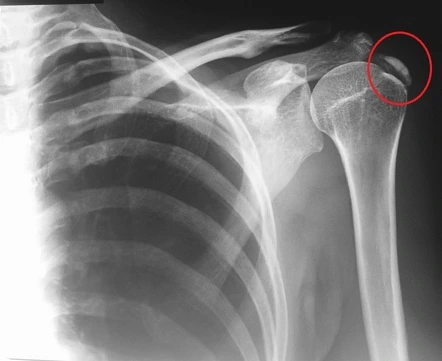

석회화 건염(calcific tendinitis)

석회화 건염은 건(힘줄) 내부에 칼슘이 축적되어 발생하는 질환으로, 주로 어깨 부위에서 많이 발생한다.

석회화되는 '건염'은 '힘줄의 염증'이 칼슘(Ca)이 쌓여 시멘트처럼 딱딱해지는 염증성 질환이다.

X-ray로 어깨를 찍어보면 위 사진처럼 어깨뼈에 하얗게 덮인 석회가 보인다.